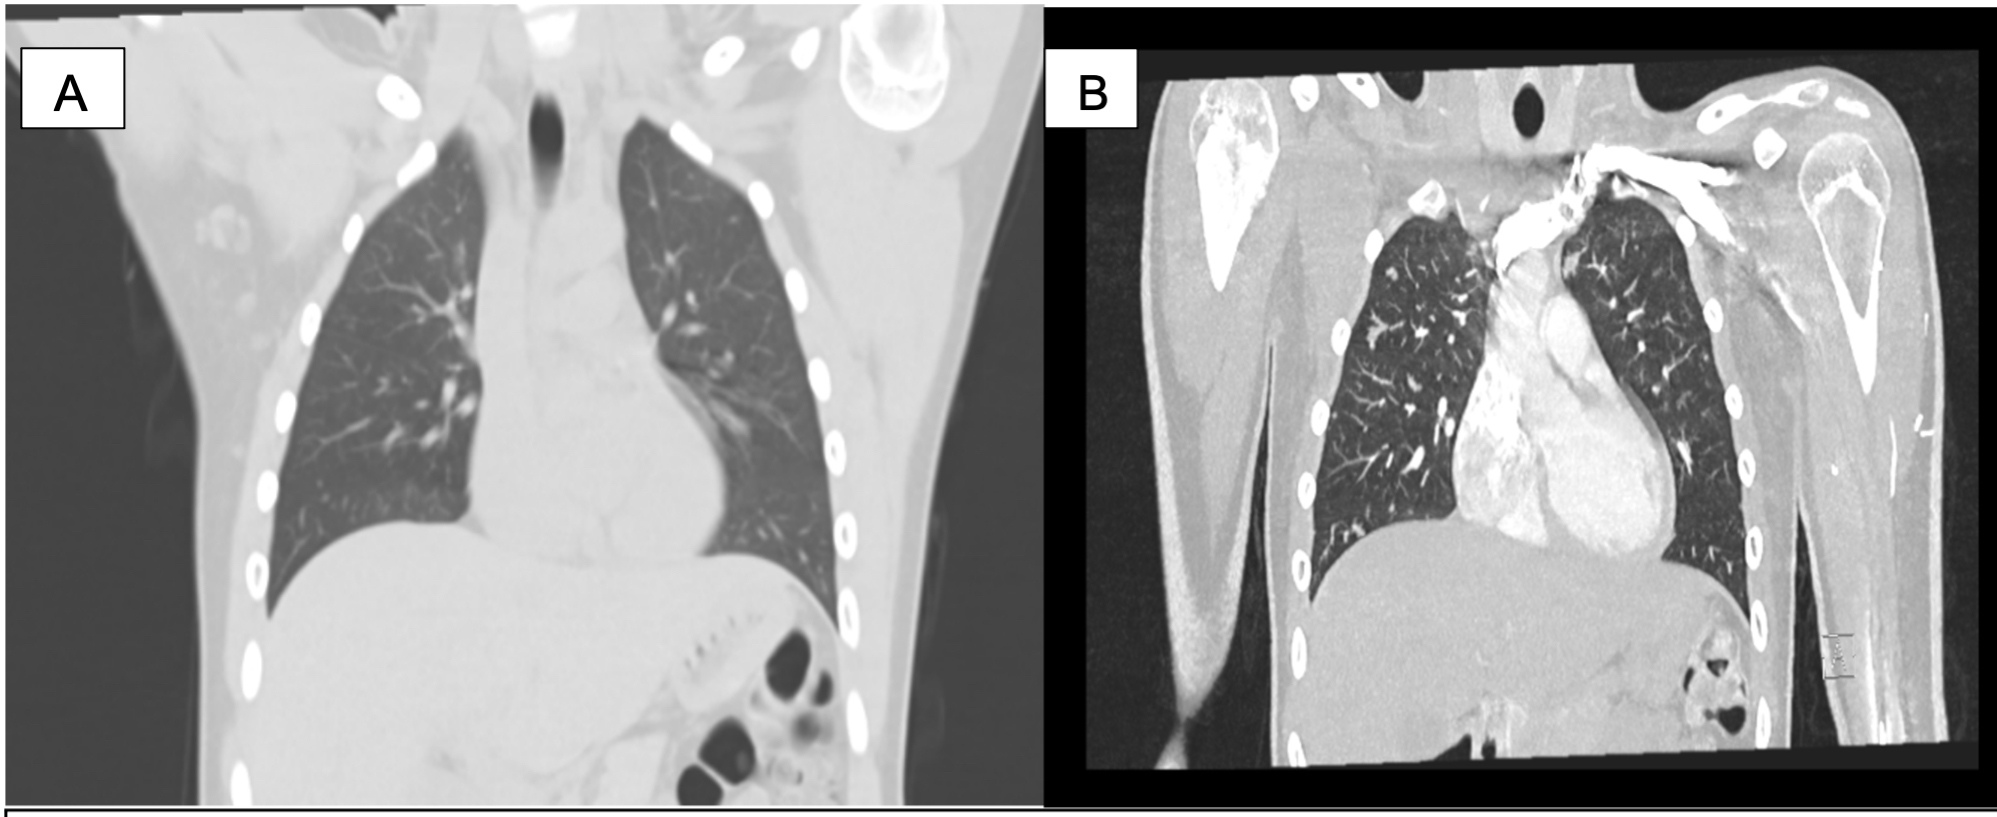

Posterior al quinto ciclo de quimioterapia se encuentra paciente estable sin dolor y se hace evaluación con imágenes RNM que reporta metástasis pulmonar (Ver figura 4), en la gammagrafía ósea (Ver figura 5) sin nuevas lesiones hipercaptantes y TAC de tórax (Ver figura 6) con imágenes nodulares pulmonares bilaterales correspondiente a metástasis pulmonar que no se observan en la evaluación inicial.

Figura 6. TAC de tórax.

A. TAC inicial normal. B. TAC de control con imágenes nodulares pulmonares bilaterales.